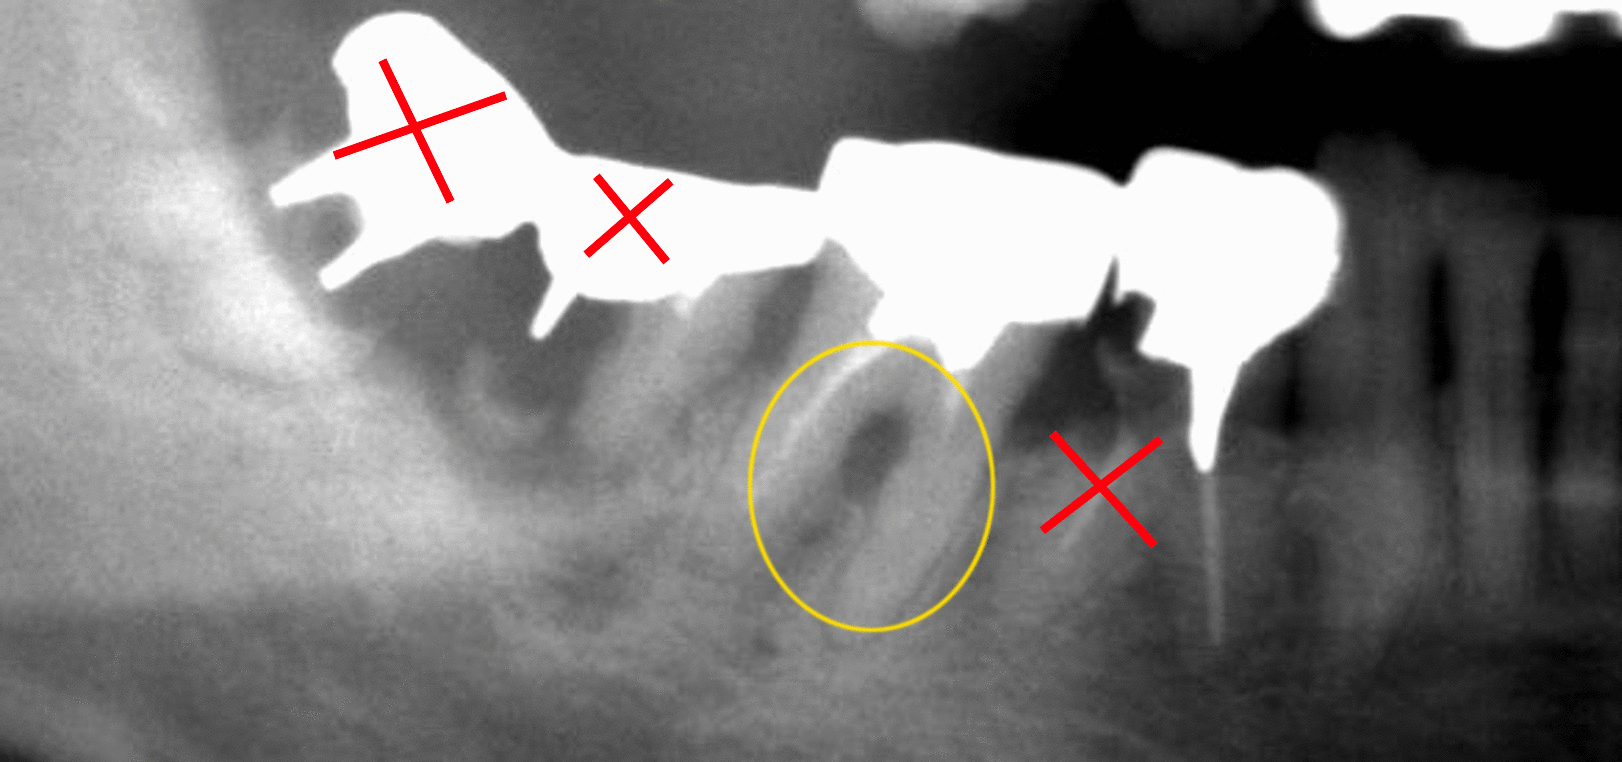

パノラマ

レントゲン写真の×マークは虫歯が深くまで進行しているため、残すことができないと診断しました。黄色◯は歯周病により歯根の分岐部の骨が吸収し、レントゲン写真に黒い影があります。ここの部分の骨の治療をする必要がありました。